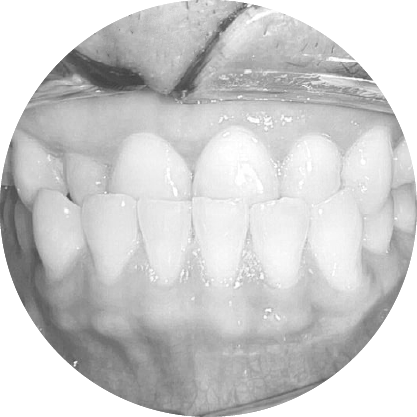

ตัวอย่างในชีวิตจริง